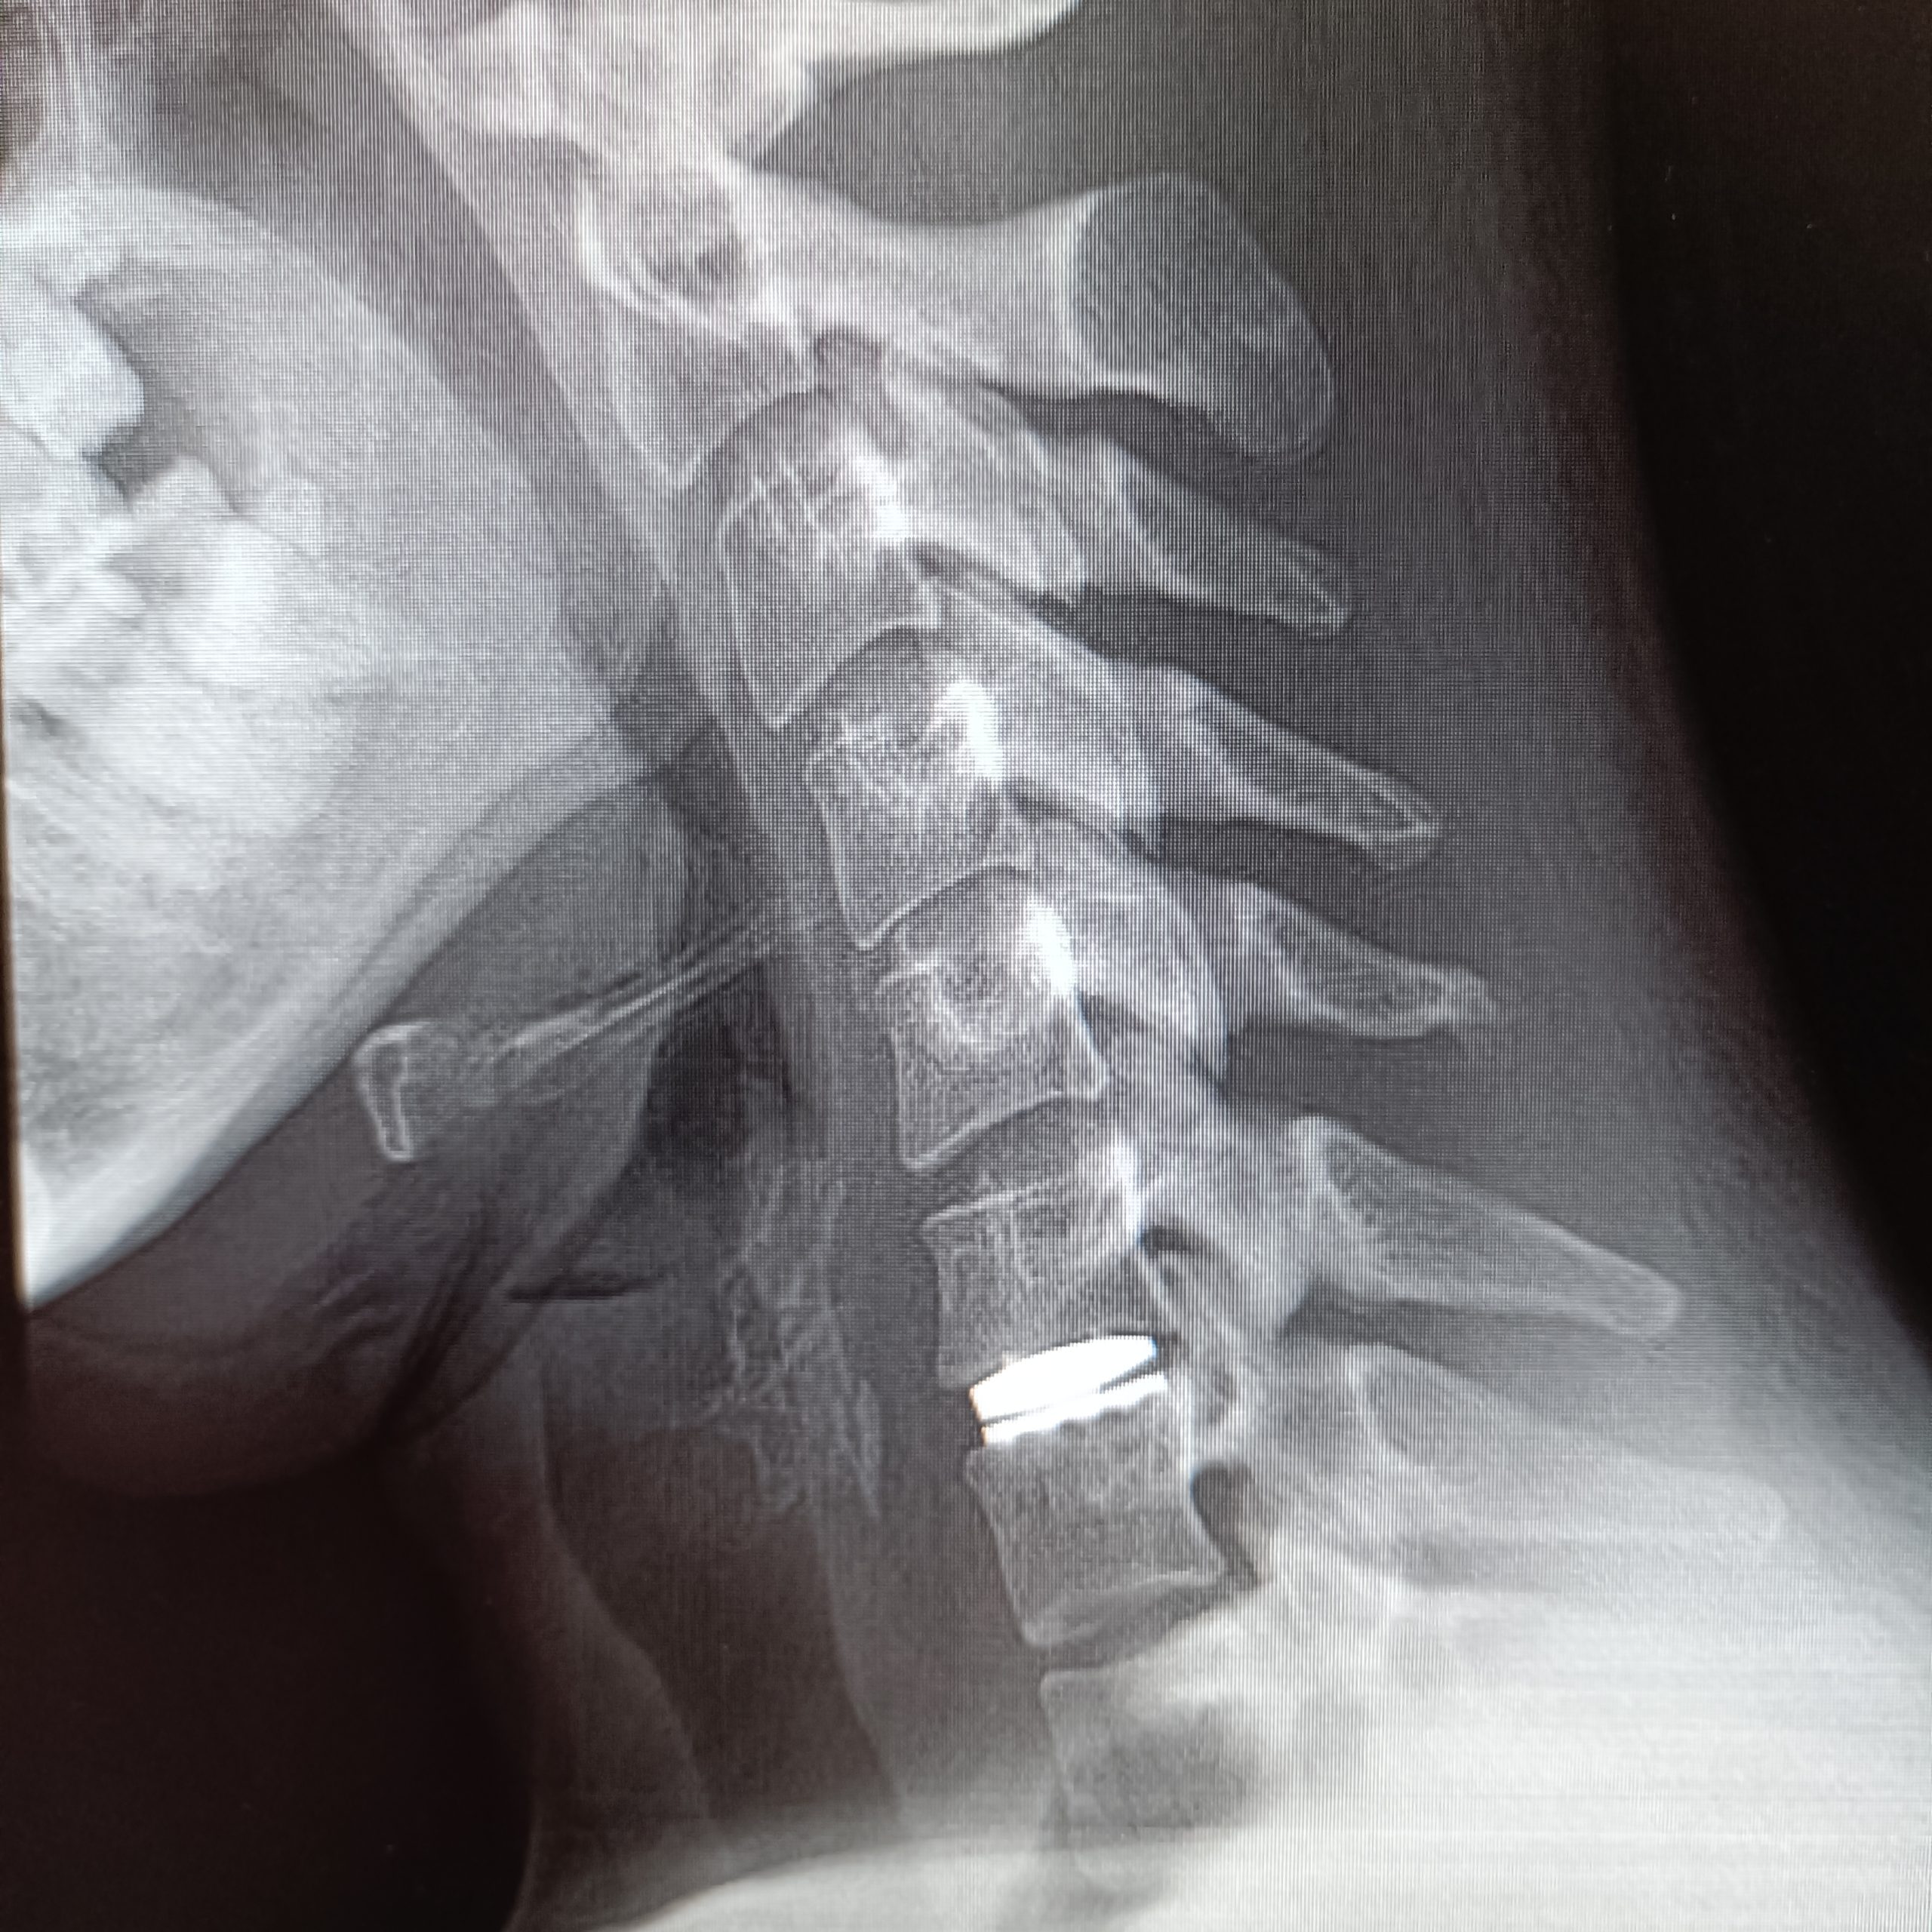

Boyun fıtığının cerrahi tedavisinde amaç, sinir kökünün üzerinde oluşan mekanik basıyı kaldırmak ve sinir kökünü rahatlatmak. Söz konusu bu bası erken dönemde kaldırıldığında sinir dokusu içerisinde daha ileri dönemlerde ortaya çıkabilecek olası kronik ve hatta kalıcı olabilecek değişikliklerin de önüne geçilmiş oluyor. Tedavi geciktiğinde ise -hasta en sonunda ameliyat olsa dahi- bu gecikmeden kaynaklı sinirde oluşan hasar nedeniyle, hastanın ameliyattan faydalanamaması söz konusu. Bu nedenle mutlaka her hasta için en doğru tedavinin ne olacağına, ne zaman ve nasıl yapılacağına karar vermek hayati önem taşıyor. Cerrahi tedavide, boynun ön veya arka tarafından yapılabilen yaklaşımlar var. Arka taraftan yapılan ameliyatlar sinir dokusunun çıktığı kanalın mikrocerrahi tekniklerle genişletilerek sinir üzerinde boyun fıtığından oluşan baskının indirekt yolla giderilmesine dayanıyor. Boynun ön tarafından uygulanan klasik cerrahide ise, iki omurga arasındaki disk tamamen çıkarılıyor ve fıtıklaşmış kısma ulaşılarak sinir rahatlatılıyor. Taşan bölüm temizlendikten sonra iki omurga arasında oluşan boşluğu doldurmak için hastanın kendi vücudunun başka bir yerinden alınan bir kemik parçası (genellikle kalçadan) veya plastik/metal kafesler kullanılıyor. Sonrasında buradaki iki omurganın birbirine tam olarak kaynaması (füzyon) için 2-3 ay beklenmesi gerekiyor. Bu tip bir ameliyat sonrasında boynun hareket kabiliyeti ameliyat edilen her bir seviye için 10-20 derece arasında azalıyor. Bu kayıp, günlük hayatta genelde bir sıkıntı yaratmasa da zaman içinde, ameliyat edilen mesafenin bir üst ile bir alt seviyesinde artan yüklenme ve esnemeye bağlı olarak boyun fıtığı oluşma riskini artırıyor. Bunun tıbbi adı “komşu segment hastalığı.” Bu risk tek seviyede yapılan klasik füzyon ameliyatlarından sonraki her yaşam yılı için %2,9. Birden çok seviyde yapılan füzyon bu yıllık riski daha da artırıyor. Yani her ne kadar başarılı olursa olsun yapılacak servikal füzyon ameliyatı sonrasında er ya da geç ikinci bir ameliyat olma olasılığı yüksek.

Günümüzde boyun fıtığı cerrahisinde hem erken dönemde hareket kabiliyetinin kısıtlanmadan en doğal şekliyle korunması hem de söz ettiğimiz “komşu segment hastalığı”nın önlenmesi açısından tercih edilen yöntem servikal disk protezleri. Bu protezler vücudun kabul ettiği, herhangi bir alerjik reaksiyon yaratmayan özel plastik ve seramik alaşımlar ile titanyum gibi hafif ve çok dayanıklı malzemelerden üretiliyor.

Servikal disk protezi kalıcı ve dayanıklı, bu yüzden ileride çıkarılması ya da değiştirilmesi gerekmiyor. Boynun doğal hareketlerini bozmadığı ve diğer sağlıklı diskleri koruduğu için de hasta açısından günlük hayatta hiçbir kısıtlamaya neden olmuyor.